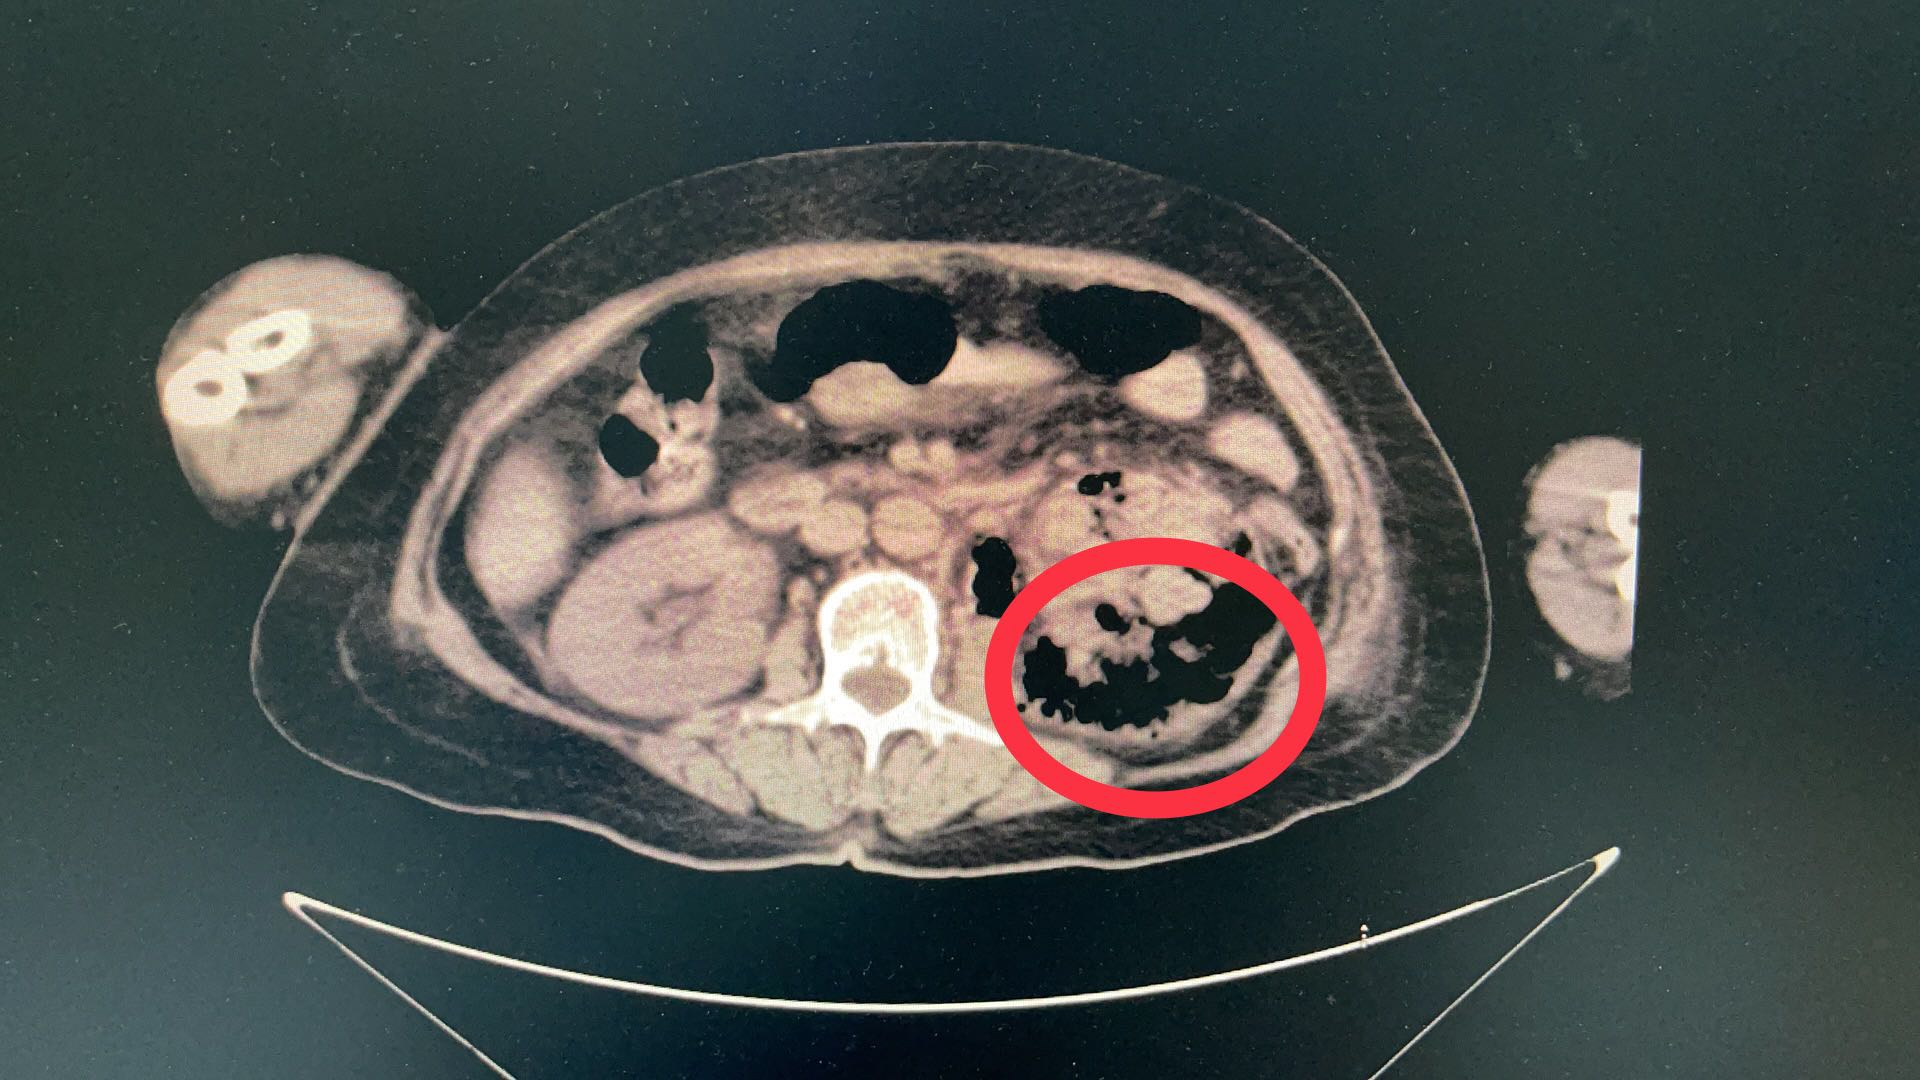

腹部ct扫描提示右肾中度积水,右输尿管扩张明显.